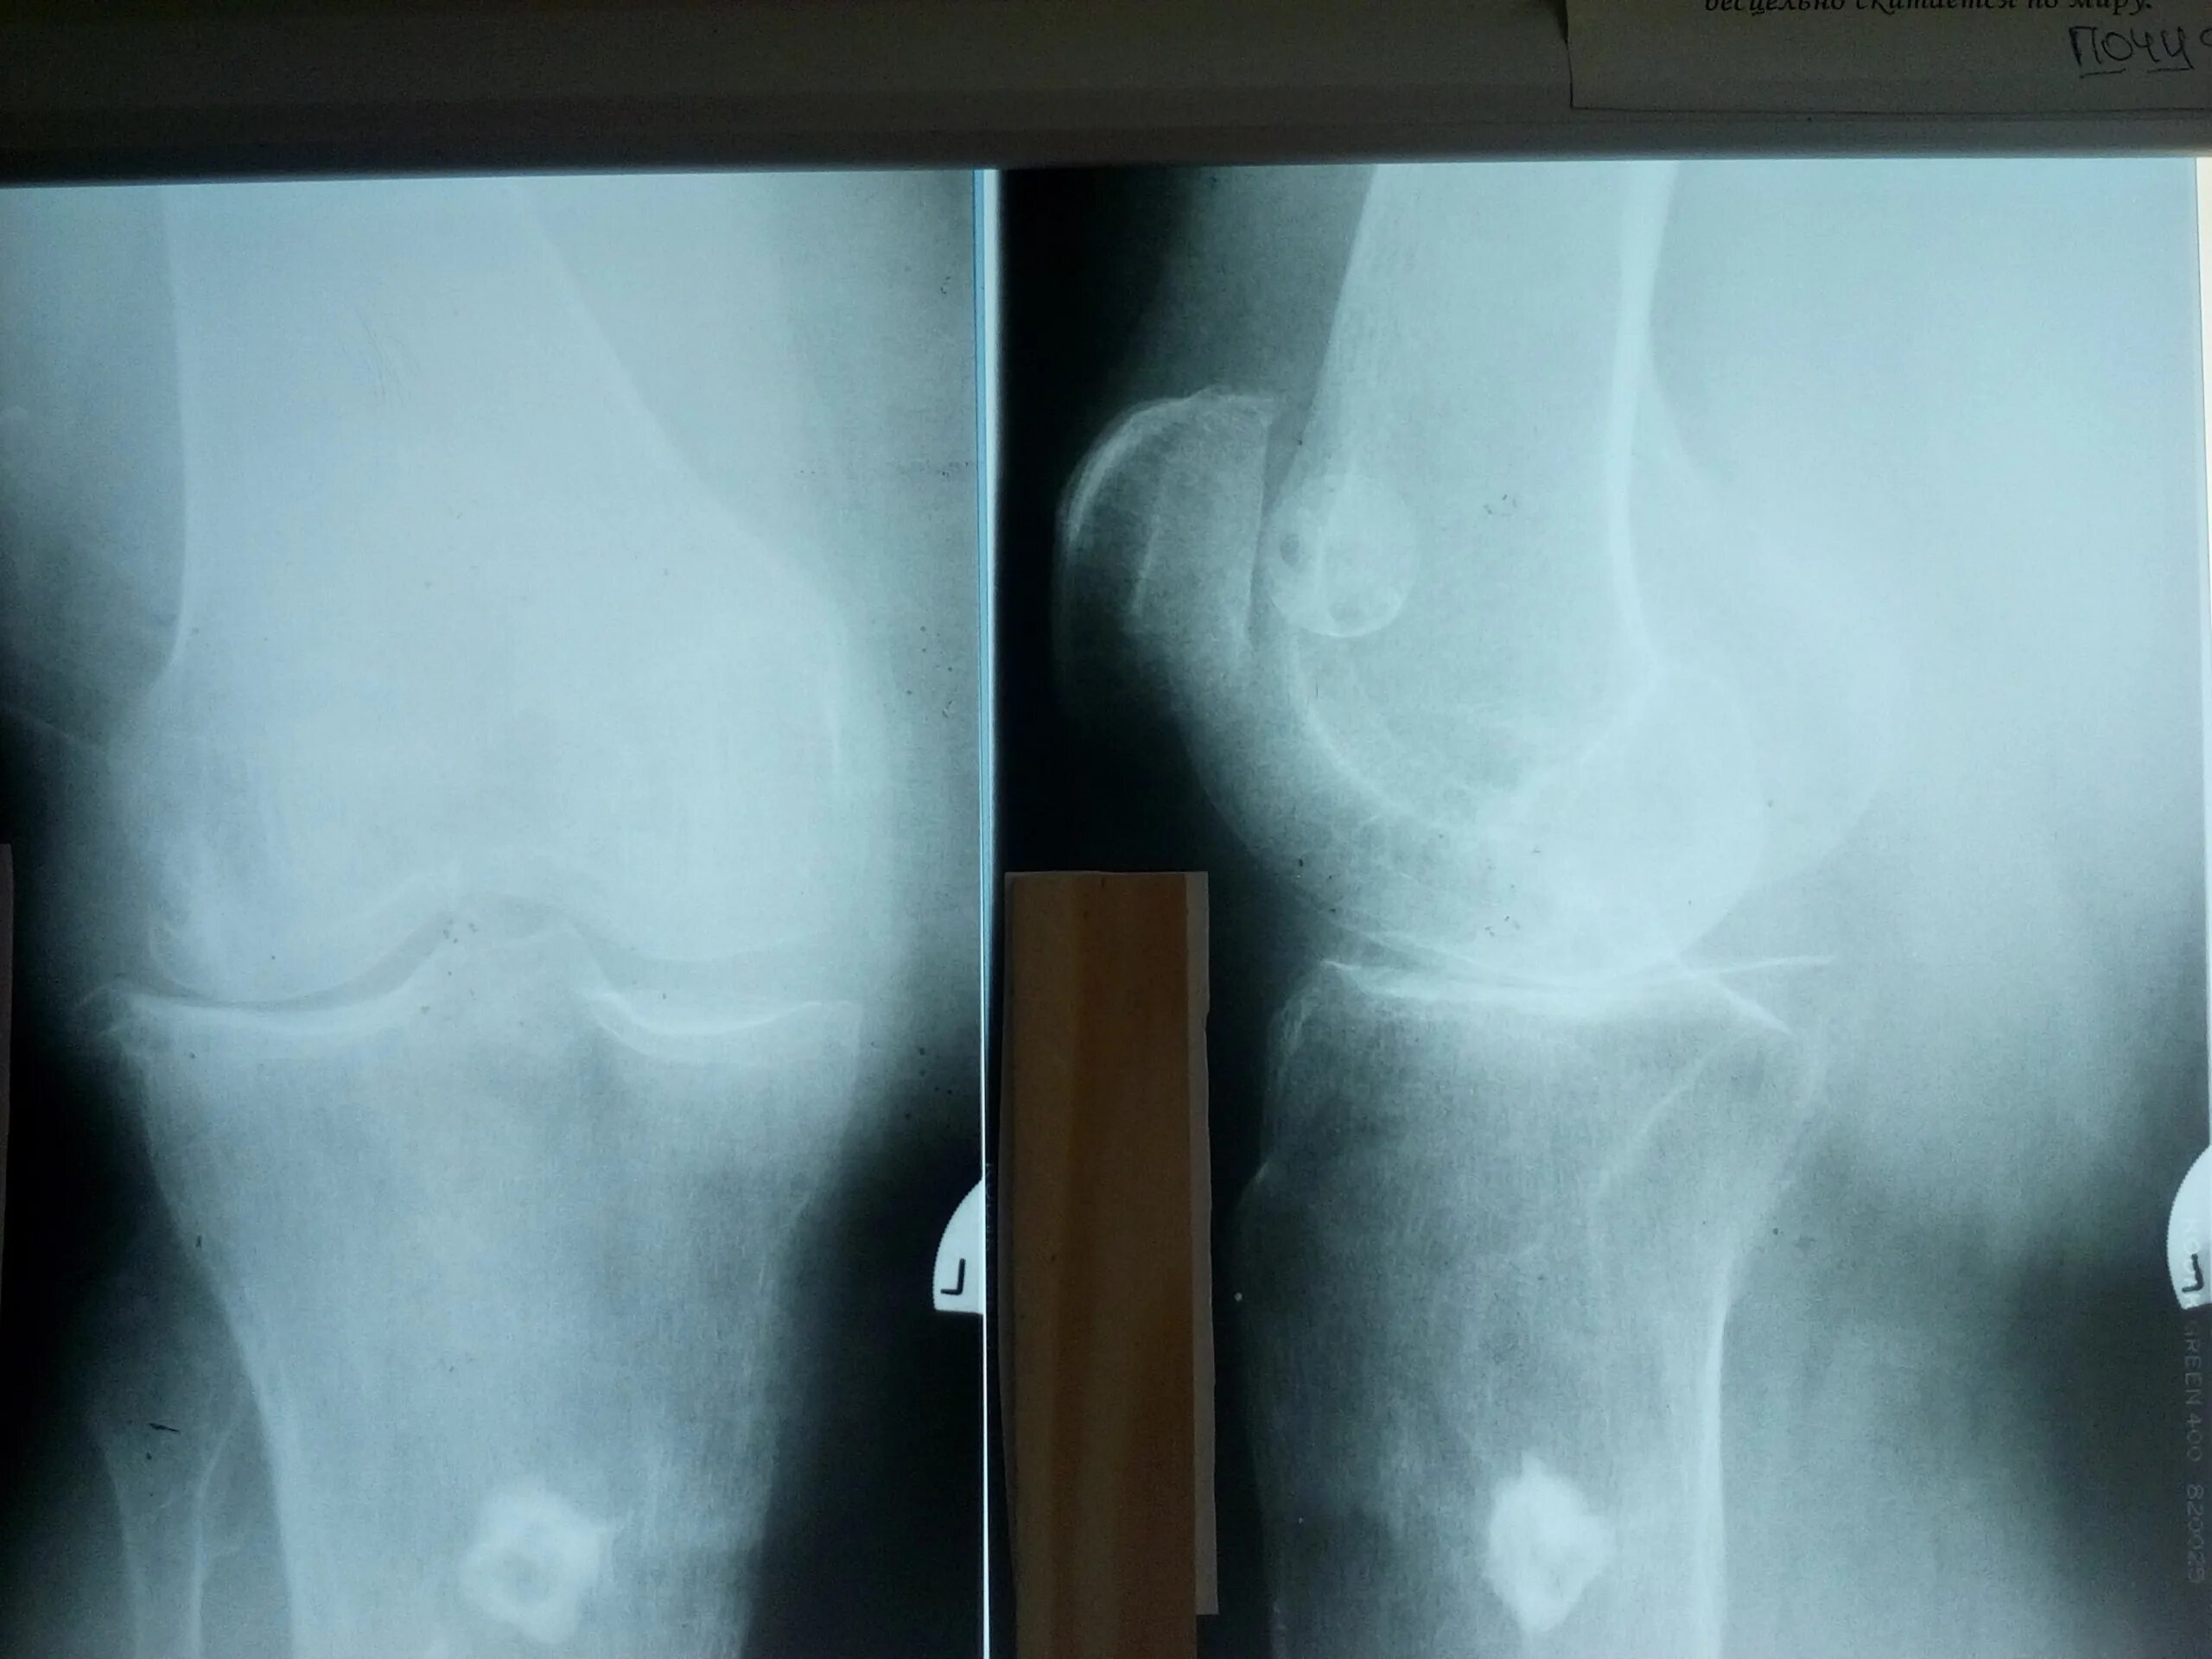

Рентгенография коленного сустава 2 проекции